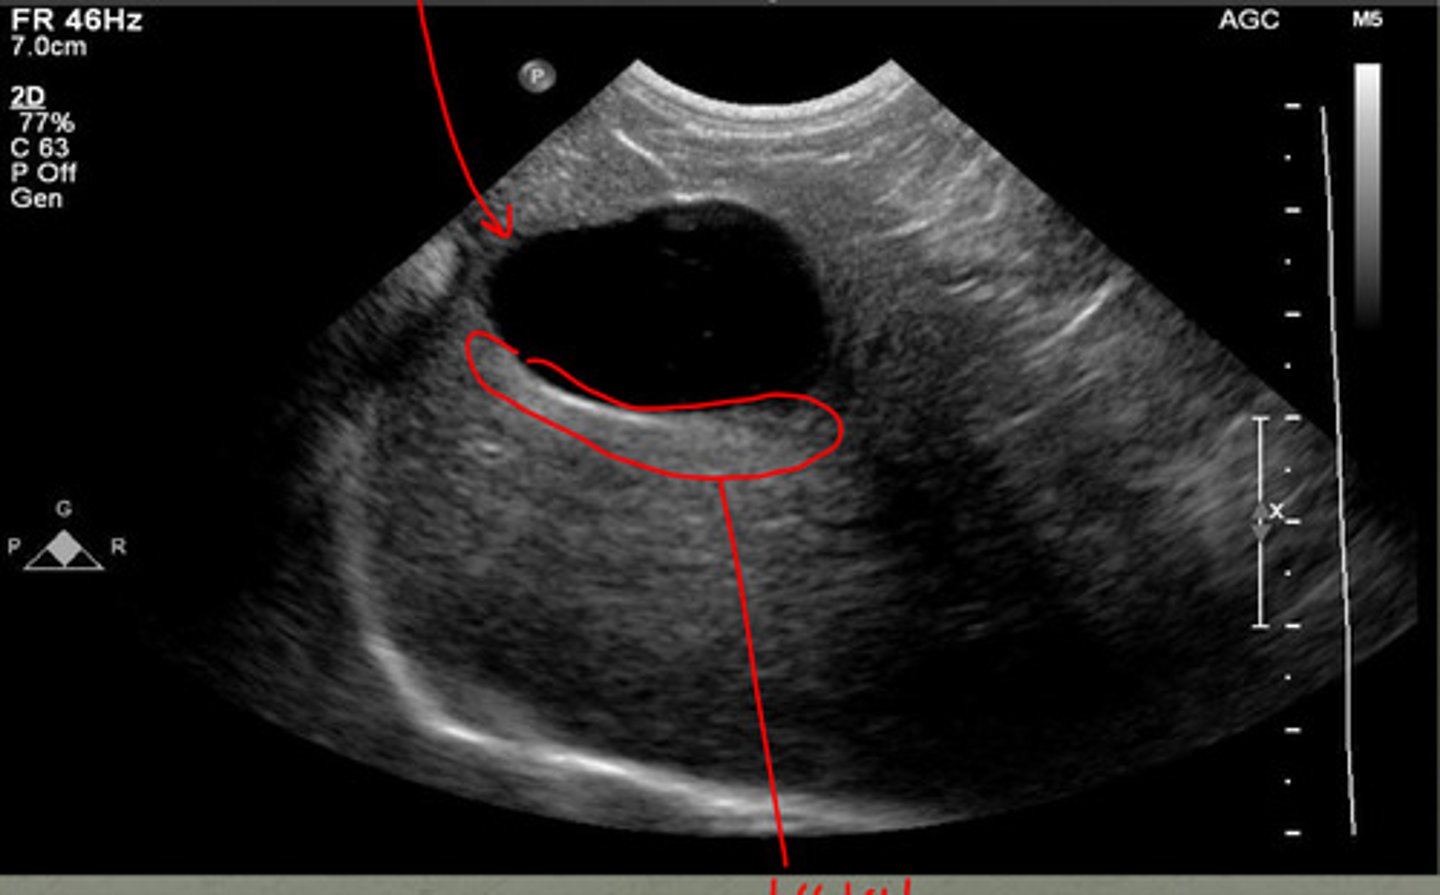

this is the spleen, just know what it looks like!!

what type of tool is being used in this ultrasound to see the different vessels?

yes, from surrounding fat

is this shadowing near the spleen normal?

shadowing underneath the mass

if there is a hyperechoic mass in the spleen, what artifact will occur due to it?

shadowing due to the splenic mass

what are the arrows indicating? (there is a mass in this spleen)